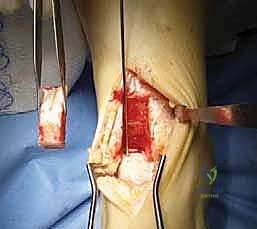

Making the Saw Cuts for the Trap Door:

- We'll use a Hall microoscillating saw with a no. 64 saw blade (Zimmer). This thin blade allows for precise, clean cuts.

- First, the two vertical parallel cuts:

- Starting from our 1-cm mark at the joint surface (angle of Hardy), make the first vertical saw cut. This cut should be 1 cm wide from the second parallel cut, and extend 3 cm in height proximally towards the anterior tibial metaphysis.

- Make the second vertical parallel saw cut, 1 cm lateral to the first, also extending 3 cm proximally.

- Ensure these cuts are 2 cm deep at the joint surface.

- These cuts should taper proximally and upward to the anterior tibial metaphysis 3 cm above the joint.

TECH FIG 2 • Saw cuts are made 1 cm wide, 3 cm high, and 2 cm deep (not seen), creating a trap door (arrow).

> **Surgical Warning:** Avoid making the vertical saw cuts more than 3 cm deep at the joint surface or 4 cm in height. Exceeding these dimensions significantly increases the risk of a medial malleolar stress fracture, which can be a debilitating complication.

* **Second, the superior horizontal cut:**

* Make a **third horizontal saw cut** connecting the upper limits of these two vertical cuts. This completes the superior border of our trap door.

* **Third, the angled inferior cut:**

* This is the critical cut that creates the "hinge" or "trap door" effect.

* Angle the saw **inferiorly and 22 degrees posteriorly** from the anterior metaphysis toward the joint surface. This creates a beveled cut, allowing the bone block to be mobilized and then replaced snugly.

- Mobilizing and Removing the Trap Door:

- Once all cuts are complete, use a thin 10-mm osteotome. Carefully insert it into the saw cuts and gently mobilize the trap door. Use controlled, light taps with a mallet if necessary.

- Once mobile, carefully remove the trap door.

- Place the bone block aside in a sterile basin, keeping it moist with saline-soaked sponges. This bone will be replaced at the end of the procedure.

TECH FIG 3 • The trap door is removed and set aside to be replaced after the graft is inserted. A probe has been inserted into the lesion (arrow).